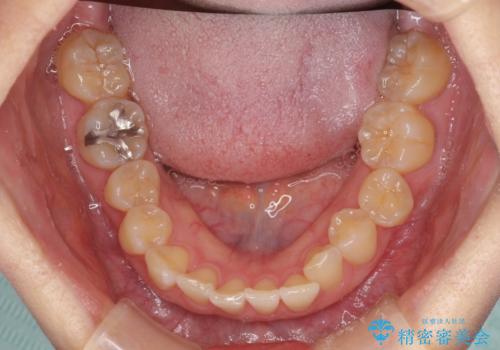

前歯のクロスバイト インビザライン矯正で改善

- むし歯治療を契機に、長年気にしていた前歯のクロスバイトの改善を希望された患者様です。

汚れが溜まりやすく、歯ぎしりがうまくできないため、インビザラインを用いて矯正治療を行うこととしました。

インビザラインによる前歯のクロスバイトの改善は、治療期間中に前歯でしか咬めない時期が続いたり、歯肉退縮や歯髄壊死のリスクが高まったりと、治療中にトラブルを抱えることがあります。

特に上顎側切歯(真ん中から2番目の歯)が舌側に引っ込んでいるケースは、インビザラインでは改善しきれないことがあると言われています。